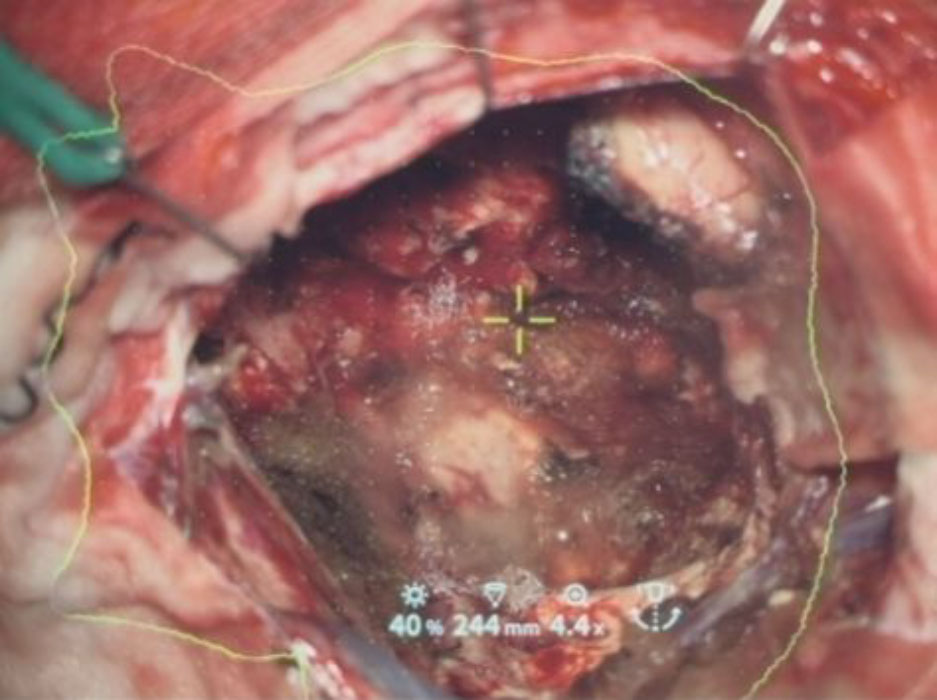

699

'25年11月

50代

左前頭葉腫瘍

頭蓋内腫瘍摘出術

No.’25_101 手術前1

No.’25_101 手術前2

No.’25_101 摘出 前

No.’25_101  摘出 中

No.’25_101 摘出 後